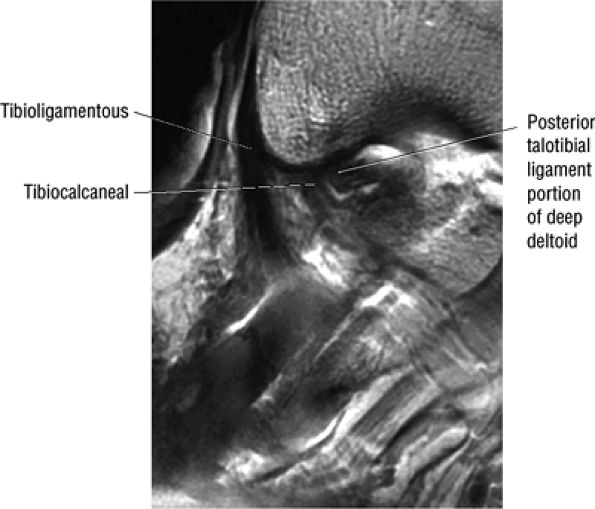

fascicle inserts onto the superior border of the calcaneona vicular ligament. The deep part of the deltoid, which is rectangular, consists of a small anterior component (the anterior tibiotalar ligament) and a strong posterior component (the posterior tibiotalar ligament) (Fig. 5.64). The posterior tibiotalar ligament represents the strongest part of the entire medial ligament complex. The deep portion of the deltoid ligament, covered by synovium, is intra-articular.

![]() |

|

FIGURE 5.58 ● transverse section through the midcalf shows the anterior and lateral compartments and their contents.